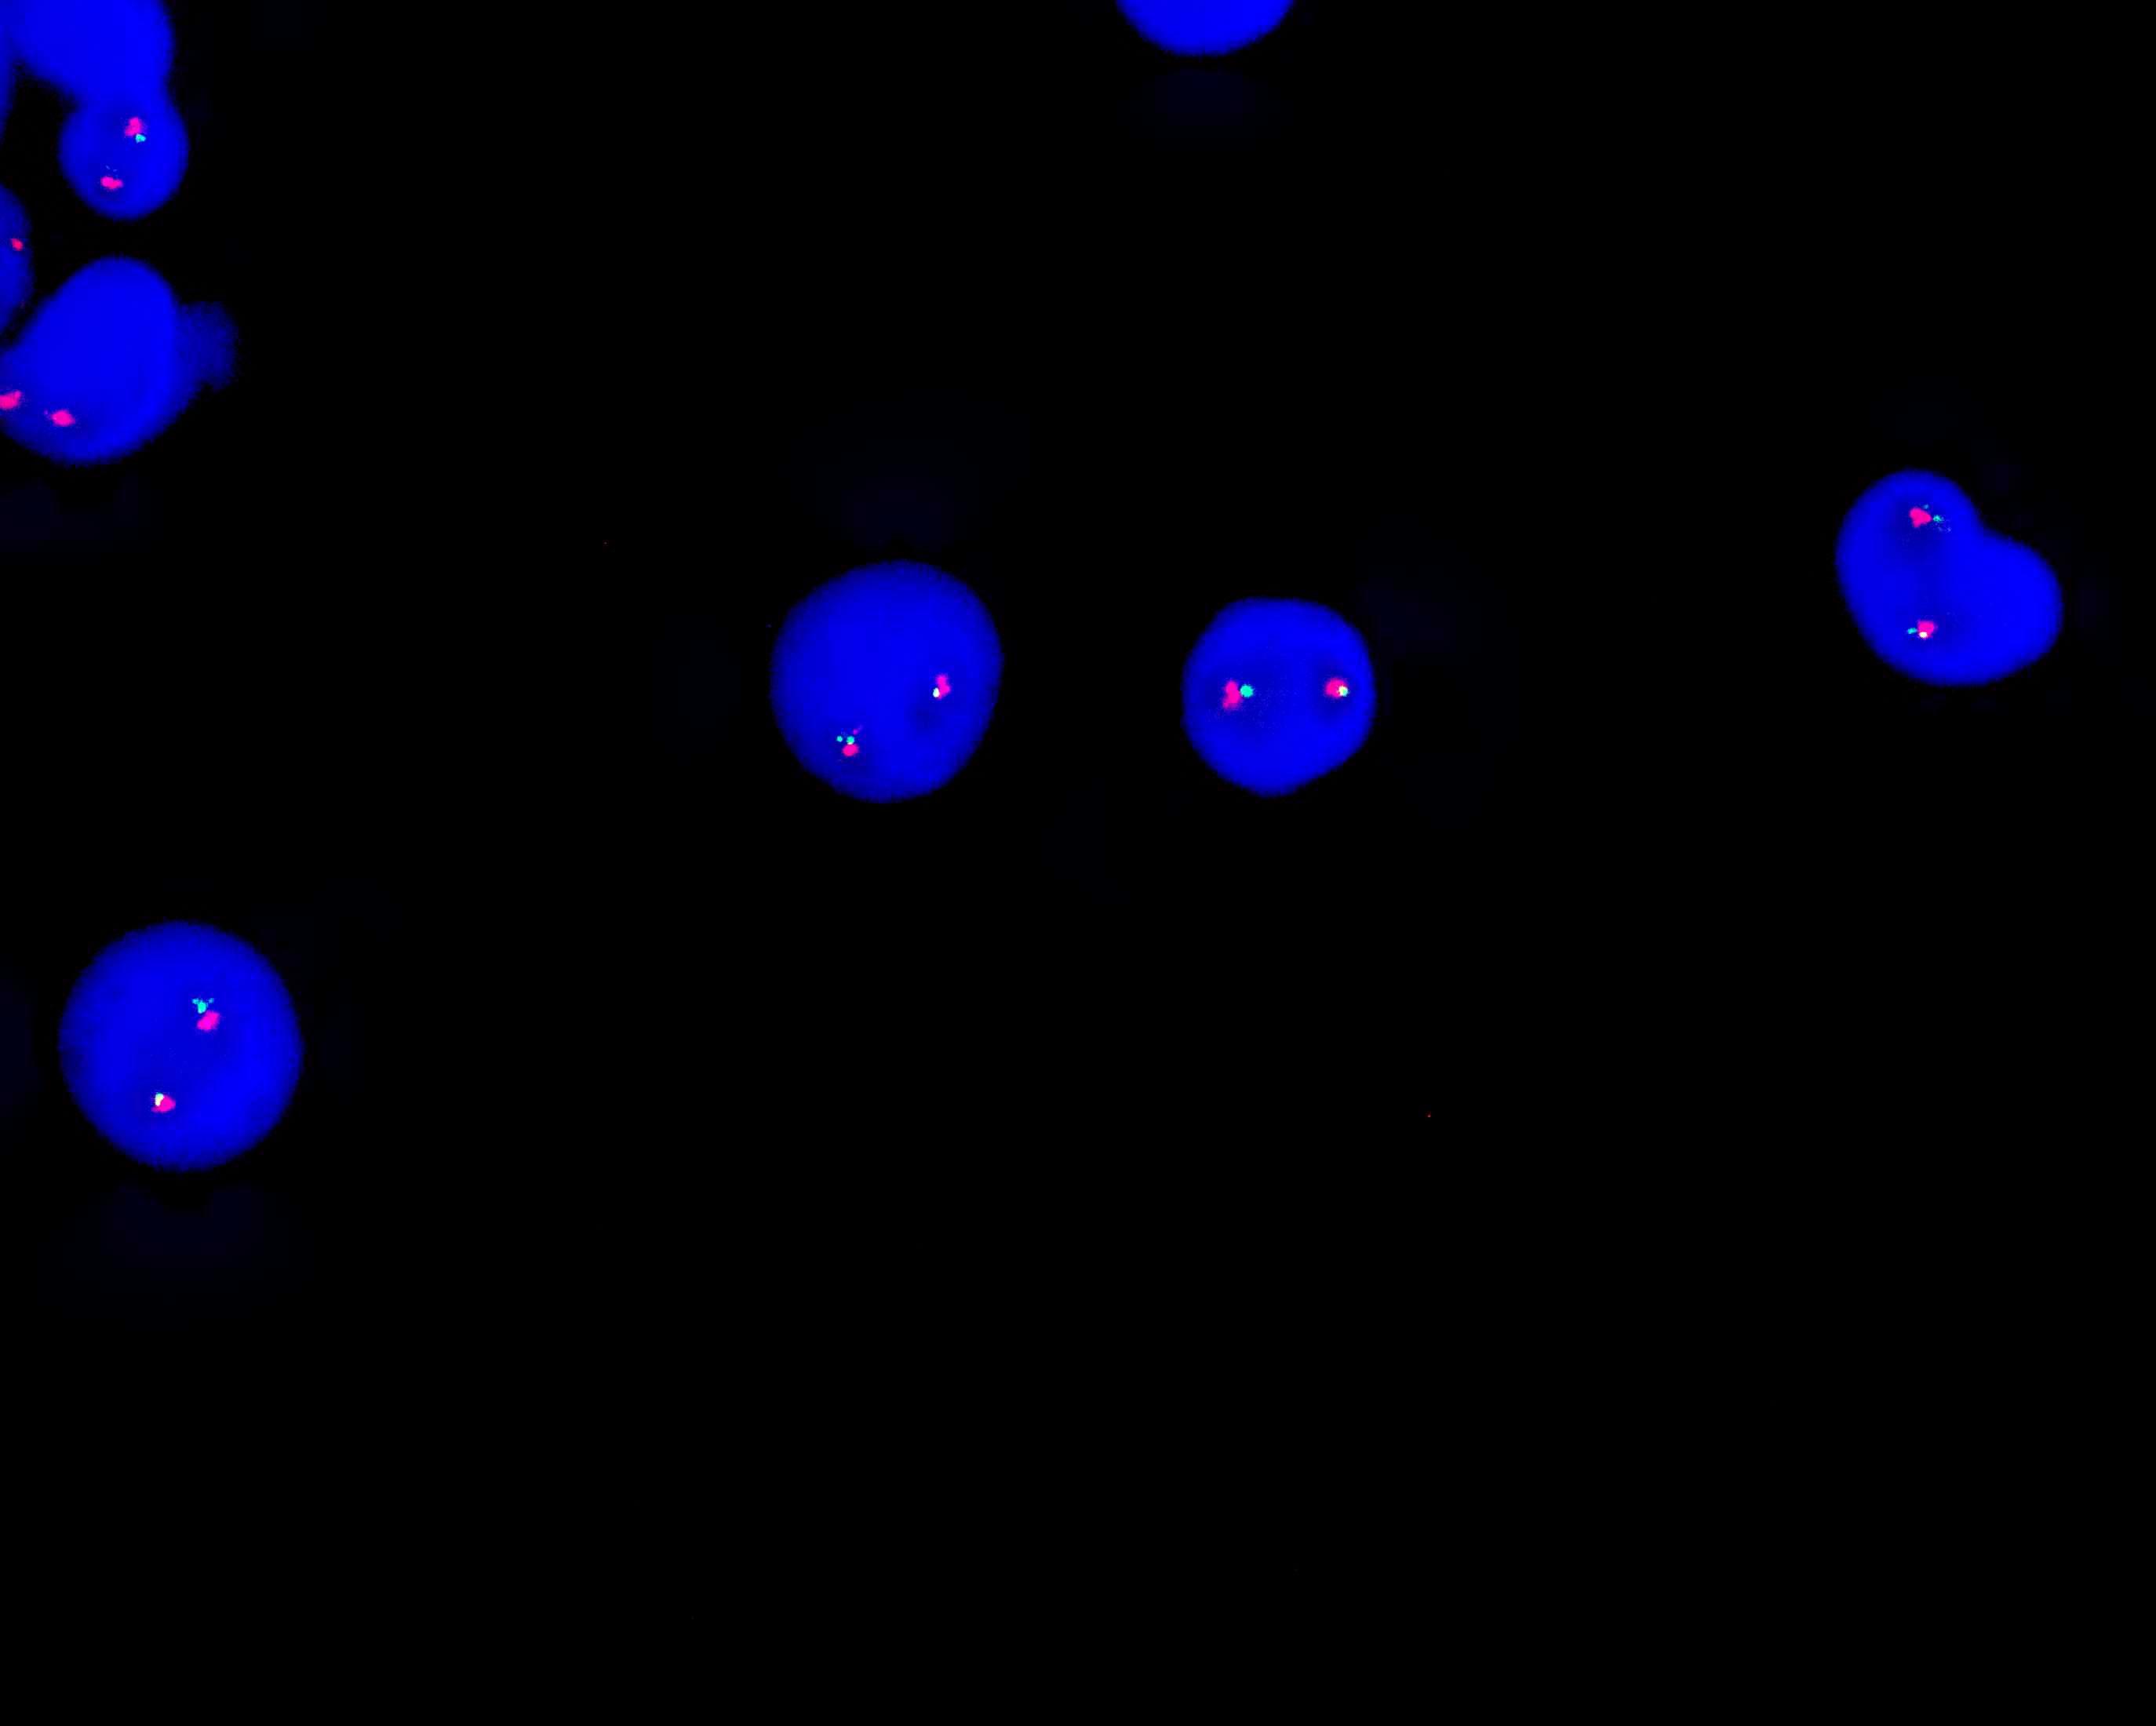

IGH dual color probe

The centromeric end of the IGH gene is labeled orange, with a length of 410 kb; the telomeric end of the IGH gene is labeled green, with a length of 530 kb.